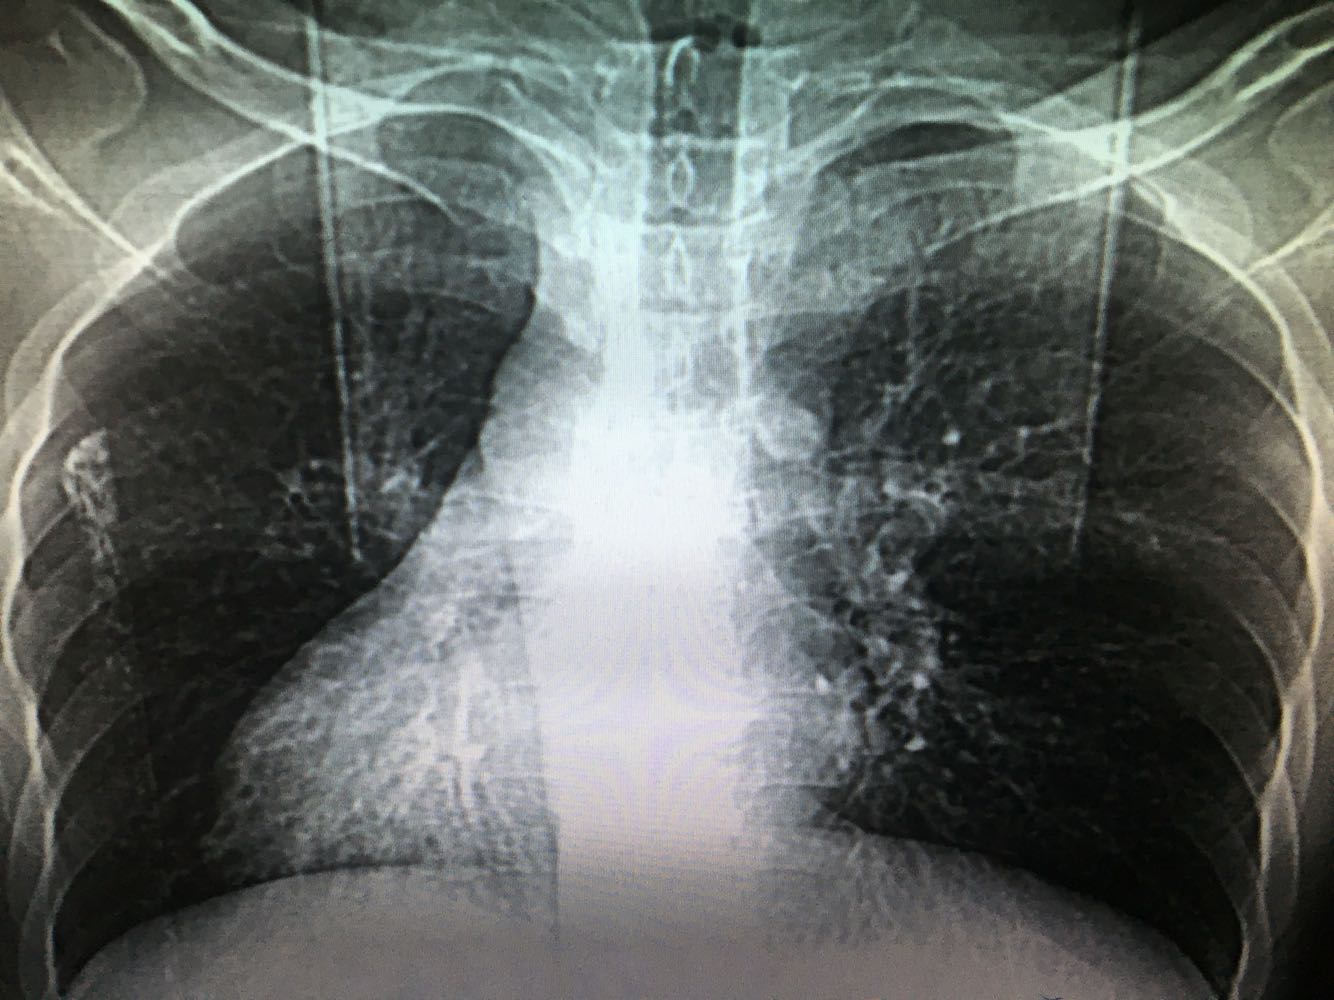

1、患者,男,33岁                                  2、主诉:咯血2天 3、现病史:患者2天前体力后出现咯血,色泽鲜红,量约100ml,无异味及异物,无胸闷气促、无头晕乏力、无腹痛腹泻、无黑曚晕厥等不适,就诊外院,查BP:130/85mmHg,血常规WBC 8.09*10^9/L,N%64.7%,HB147g/L,PLT180*10^9/L。胸部CT:两肺下叶及左肺上叶舌段支气管扩张。未予特殊处理,嘱休息随访,患者回家2小时后再次出现上述症状,呕吐鲜红色血伴血块,遂就诊我院,为求进一步诊疗,收治入院。 4、既往史:既往有支气管扩张、右位心、慢性鼻炎病史,否认高血压、糖尿病,否认乙肝结核等传染病史,否认食物、药物过敏史

查体:神清,精神可,T36.8℃,BP:130/85mmHg,对答切题,双侧瞳孔等大等圆,直径3mm,对光反射存在,皮肤及巩膜无黄染,无贫血貌,浅表淋巴结未及肿大,颈软,气管居中,双肺呼吸音清,可闻及湿罗音,心率80次/分,律齐,无杂音,腹平软,无压痛,无反跳痛及肌紧张,肝脾肋下未及,未见明显胃肠型蠕动波,肠鸣4次/分,未及明显肿块,肝肾叩击痛(-),移动性浊音阴性,双下肢无水肿,神经系统检查(-)

诊断:支气管扩张咯血,右位心,慢性鼻炎                                                              治疗:入院后完善检查,予抗感染,保肝,护胃,止血、化痰、补液等对症支持治疗。